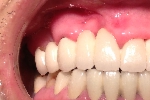

患者さんが移植を望まなかったので骨の増生行いませんでしたがポケットも消失し現在も良好な状態を保っています。